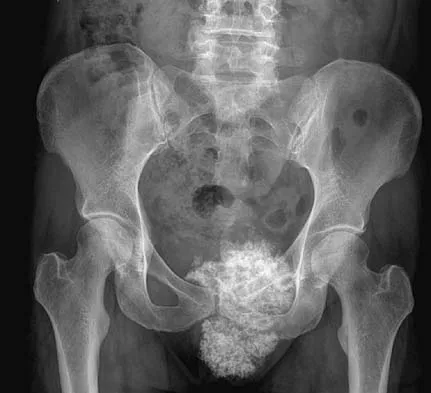

A 47-year-old woman has an asymptomatic pelvic mass that was discovered on routine gynecologic examination. A radiograph, CT scan, MRI scan, and biopsy specimen are shown in Figures 7a through 7d. Metastatic work-up is negative. Treatment should consist of

The imaging studies show a chondrosarcoma; therefore, surgical treatment is indicated. There is no role for intralesional treatment of an exophytic lesion, particularly in the pelvis. Even obtaining a biopsy specimen risks intrapelvic contamination, although many surgeons would still perform a biopsy prior to a resection to confirm the diagnosis. Chondrosarcoma is considered resistant to both radiation therapy and chemotherapy; therefore, radiation therapy generally is not used except for unresectable lesions. Chemotherapy would be used only for metastatic disease or in patients with high-grade chondrosarcoma. The grade would not be known until after resection, and in this patient, the histology slide showed a grade I neoplasm. Chemotherapy would not be used preoperatively because a cartilage tumor is unlikely to shrink, and in this patient, the lesion is resectable. Springfield DS, Gebhardt MS, Mcguire MH: Chondrosarcoma: A review. J Bone Joint Surg Am 1996;78:141-149.